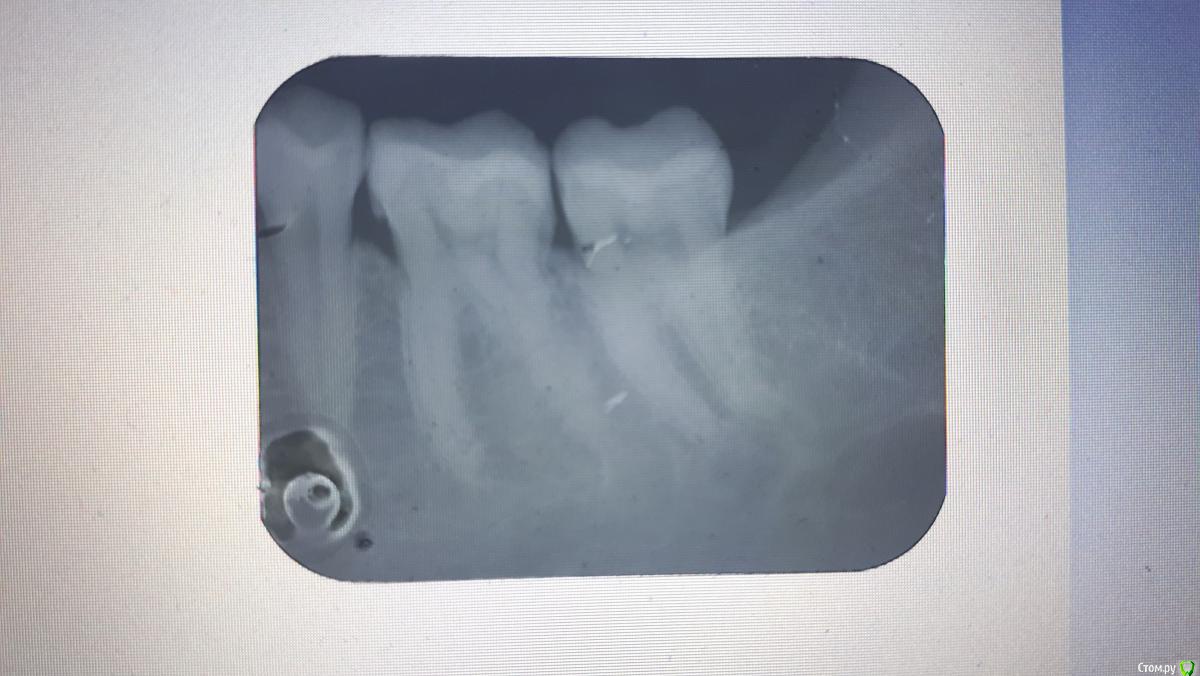

Яковлева Ксения Опубликовано 28 июля, 2019 Поделиться Опубликовано 28 июля, 2019 (изменено) Здравствуйте, уважаемые врачи! 3 недели назад мне запломбировали глубокий кариес в 6 и 7 нижних зубах с правой стороны. До этого эти зубы не беспокоили и не болели. И вот уже 3 недели меня беспокоют ноющие боли. Болит как в течение дня, так и вечером. Когда ем, то твердую пищу больно пережевывать этой стороной, Но болит терпимо. Стоматолог, который пломбировал, считает что так реагирует именно 7 зуб. Он также чувствителен на холодную пищу, на горячее не реагирует. Пломбу уже дважды подпиливали по прикусу, покрывали специальным составом для снижения чувствительности. Я также принимала нимесил в течение 5 дней по рекомендации врача для снижения боли и чистила зубы Сендодином. По рентгену стоматолог сказал, что все хорошо, но если будет и дальше так зуб беспокоить, то стоит его депульпировать (рентген прилагаю). 27.07.2019 я пошла в частную поликлинику, где мне сделали прицельную компьютерную томографию, которая показала, что пломбы как бы не плотно прилегают к зубу. Стоматолог в частной клинике предложил перелечить пломбы. После приема вечером правая сторона разболелась сама по себе, отдавая то в верхнюю челюсть, то под нижнюю челюсть, то в область уха. Болел где-то с 23:30 до 01:30 ночи. Имеет ли смысл перелечивать пломбы на причинных зубах или это пульпит и стоит просто депульпировать 7 зуб? И если перелечивать, не рассверлят ли мне еще глубже полости когда будут снимать пломбы и не приведет ли это к пульпиту? Буду очень признательна вам за консультацию. Фотографии проекций КТ прилагаю. Стрелочками карандашом показаны проблемные места на зубах. Изменено 28 июля, 2019 пользователем Яковлева Ксения Ссылка на комментарий